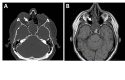

Methods: A 54-year-old man presented with nasal mass. Endoscopic resection showed a low-grade spindle cell neoplasm with morphologic features of BSS and immunohistochemical and next generation sequencing were performed to confirm the diagnosis.